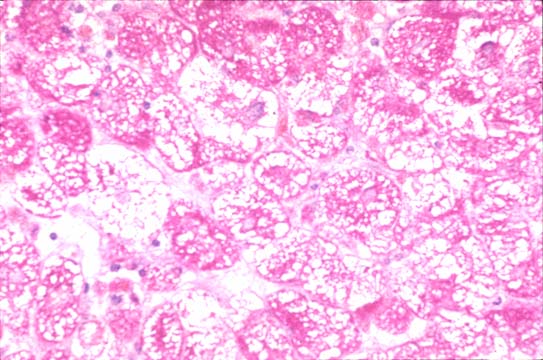

Fig 36 - Fat in macrovesicles

peripheral nuclei,

no cellular damage